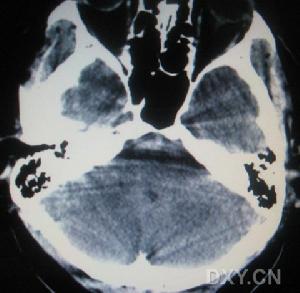

(2)cT掃描不僅可以直接顯示血腫大小和部位,還可以了解腦室受壓和中線結構移位的程度及並存的腦挫裂傷、腦水腫等情況,應及早套用於疑有顱內血腫患者的檢查。硬腦膜外血腫cT表現為顱骨內板與硬腦膜之間的雙凸鏡形或弓形高密度影;急性或亞急性硬腦膜下血腫cT表現為腦表面新月形高密度、混雜密度影,多伴有腦挫裂傷和腦受壓;腦內血腫表現為腦挫裂傷區附近或腦深部白質內類圓形或不規則高密度影。

(3)、腦內(包括腦室內)血腫系指血腫形成於腦實質內或腦室內者。腦內淺部血腫多由於挫裂的腦皮質血管破裂所致,常與硬腦膜下血腫同時存在;腦內深部血腫系腦深部血管破裂所引起,腦表面無明顯挫裂傷。